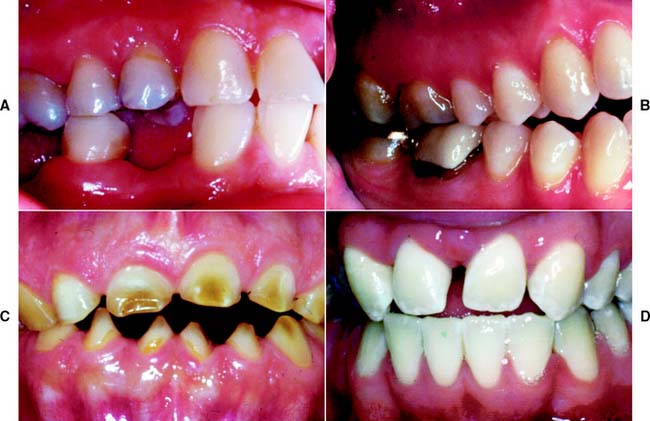

There are significant differences in the adaptive response of patients to occlusal abnormalities. Some individuals are unable to tolerate seemingly trivial occlusal deficiencies, whereas others are able to tolerate distinct malocclusions without obvious symptoms (Fig. 4-22). Most patients seem able to adapt to small occlusal deficiencies without exhibiting acute symptoms.

Fig. 4-22 Patient adaptability: None of the four patients described here expressed any concern about their occlusion. A, Anterior esthetics motivated a 45-year-old woman to seek treatment, although loss of posterior occlusal contact probably contributed to the development of her anterior diastema. B, A 26-year-old woman had no complaints or neuromuscular symptoms, despite contacting only on her second and first molars. C, A patient with amelogenesis imperfecta sought care for esthetic reasons rather than functional complaints. D, A 21-year-old man with congenitally missing lateral incisors had neither functional nor pain complaints when he was referred for fixed prosthodontic care after orthodontic treatment.